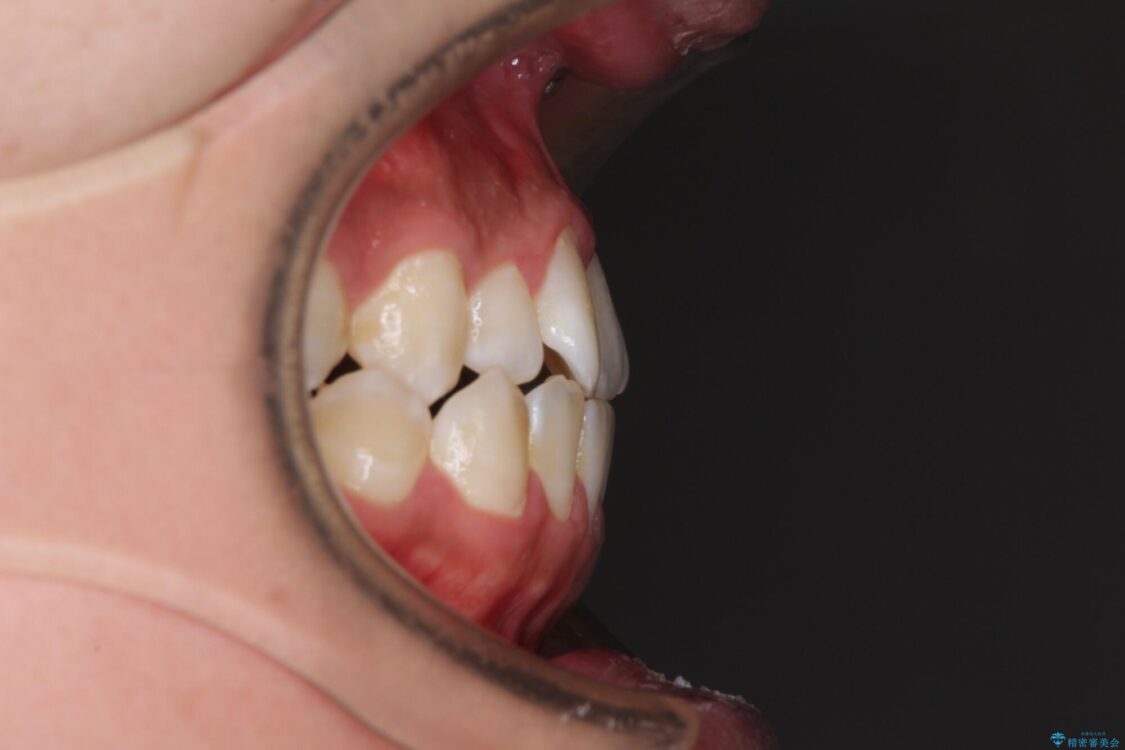

治療前

• 前歯の反対咬合 非抜歯のワイヤー矯正 治療前画像